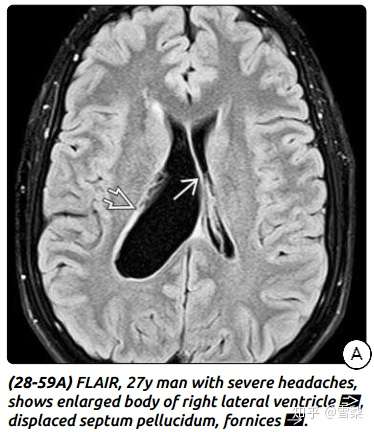

ependymalcyst室管膜囊肿